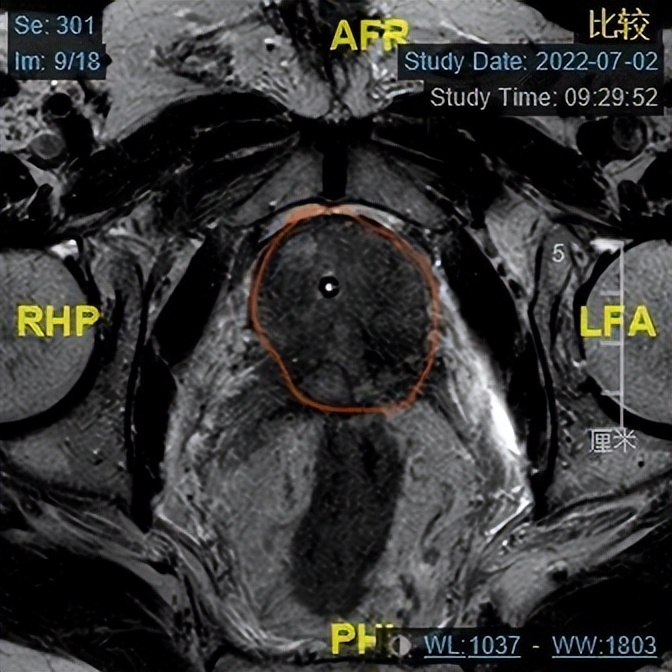

年近7旬的杨大爷,3个月前在当地医院发现自己患前列腺癌后,每天心事重重,失眠,家属看到杨大爷每天这种状态也心急如焚,在多方了解下找到哈医大一院泌尿外科王春阳教授寻求治疗。住院后完善相关检查,TPSA>100ng/mL,前列腺MRI考虑前列腺癌,侵及双侧精囊,前列腺大小约37g,结合病史及检查,杨大爷前列腺癌已是局部晚期,需即刻行手术治疗,但手术风险高,效果差,建议先行新辅助内分泌治疗,再行手术治疗。

出院后杨大爷定期使用新辅助内分泌治疗,3个月后再次到我院就诊,复查TPSA及前列腺MRI,TPSA降至0.06ng/mL,游离PSA/总PSA为0.32,前列腺MRI提示病变与3个月前比较,病变范围缩小,前列腺大小约18g,与3个月前相比明显缩小。王春阳主任认为杨大爷现在行手术治疗,术后效果能达到预期。

第一次前列腺MRI